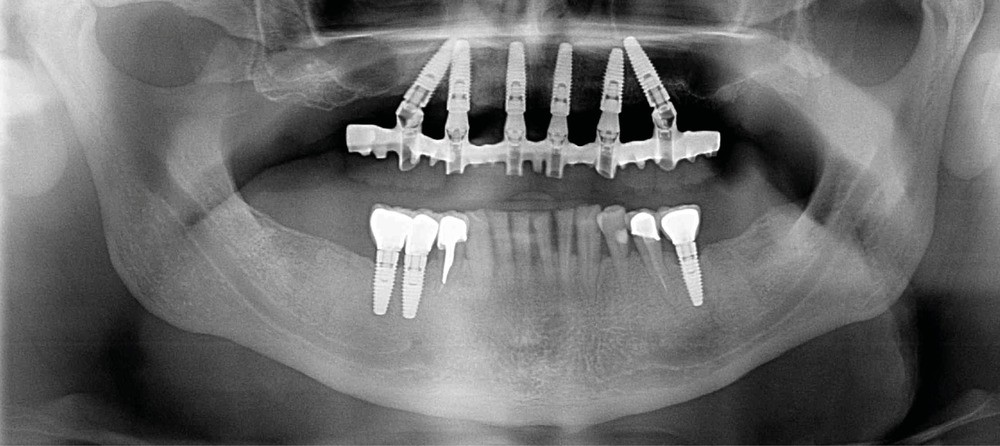

Des extractions multiples, simultanées ou graduelles, auront des répercussions sur les dents restantes et sur les tissus mous.

En effet, en cas d’extractions multiples, il est fréquent de constater une diminution de la dimension verticale et une perlèche labiale. Il s’agit d’une chéilite angulaire, liée à des perturbations de la coaptation labiale. Elle est un peu similaire à celle retrouvée chez les patients édentés complets chez qui la dimension verticale est sur- ou sous-évaluée [15].

Des extractions multiples non compensées peuvent aussi occasionner une usure excessive des dents restantes, en raison de leur sollicitation occlusale trop importante.

La prise en charge de ces édentements nécessite un examen complet du site implantaire et de l’environnement [16]. Les conséquences du non-remplacement rapide que nous venons d’énumérer sont à prendre en compte et à corriger pour une intégration optimale de la restauration prothétique implantaire. Ainsi, des corrections orthodontiques peuvent être nécessaires avant ou pendant la thérapeutique implantaire.

Le temps de l’ostéointégration, des versions ou migrations sont aussi possibles et le recours à des dispositifs de maintien de l’espace peut se révéler indispensable (fig. 22 et 23).